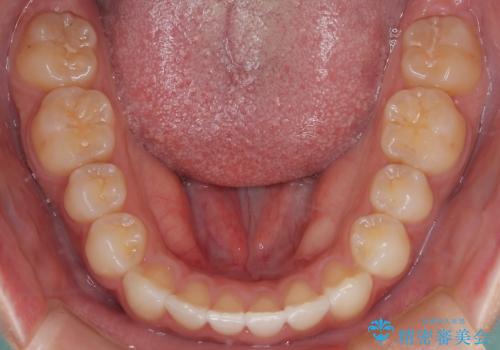

- 前歯の叢生を主訴に来院されました。非抜歯でインビザラインで治療をしました。

叢生はIPRをし、並べました。この患者様はオープンバイトだったため歯を並べる過程でかみ合わせも治しました。